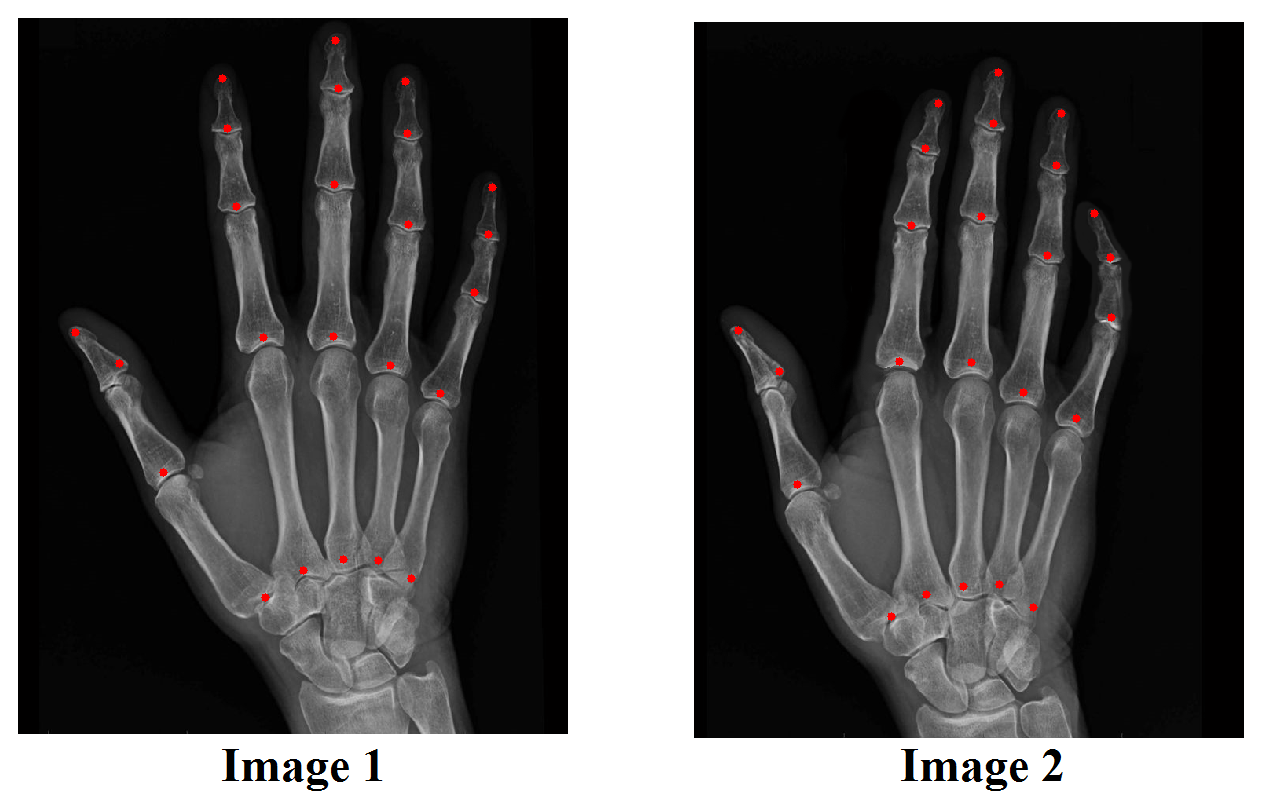

Example 7

We test the hybrid registration algorithm on real images. Figure 12 shows two images of the human hands. Corresponding landmark features are labeled on each images. In Figure 13, we show the registration results using different approaches. Figure 13(B) shows the deformed image from Image 1 using the landmark based registration model. Notice that if we only use landmarks as constraints to guide the registration, the deformed image is very different (see regions in the red boxes) from the target image (as shown in (A)). (C) shows the deformed image from Image 1 using the intensity based registration model. Similarly, the deformed image is very different (see regions in the red boxes) from the target image if only intensity information is used. (D) shows the deformed image from Image 1 using the proposed hybrid registration model. The deformed image closely resembles to the target image. In fact, the intensity mismatching error is less than 1%, meaning that the registration is very accurate.

Refer to caption

Fig. 13: Registration results of the human hand images using different approaches. (A) shows the target image (Image 2 as in Figure 12). (B) shows the deformed image from Image 1 using the landmark based registration model. (C) shows the deformed image from Image 1 using the intensity based registration model. (D) shows the deformed image from Image 1 using the proposed hybrid registration model.